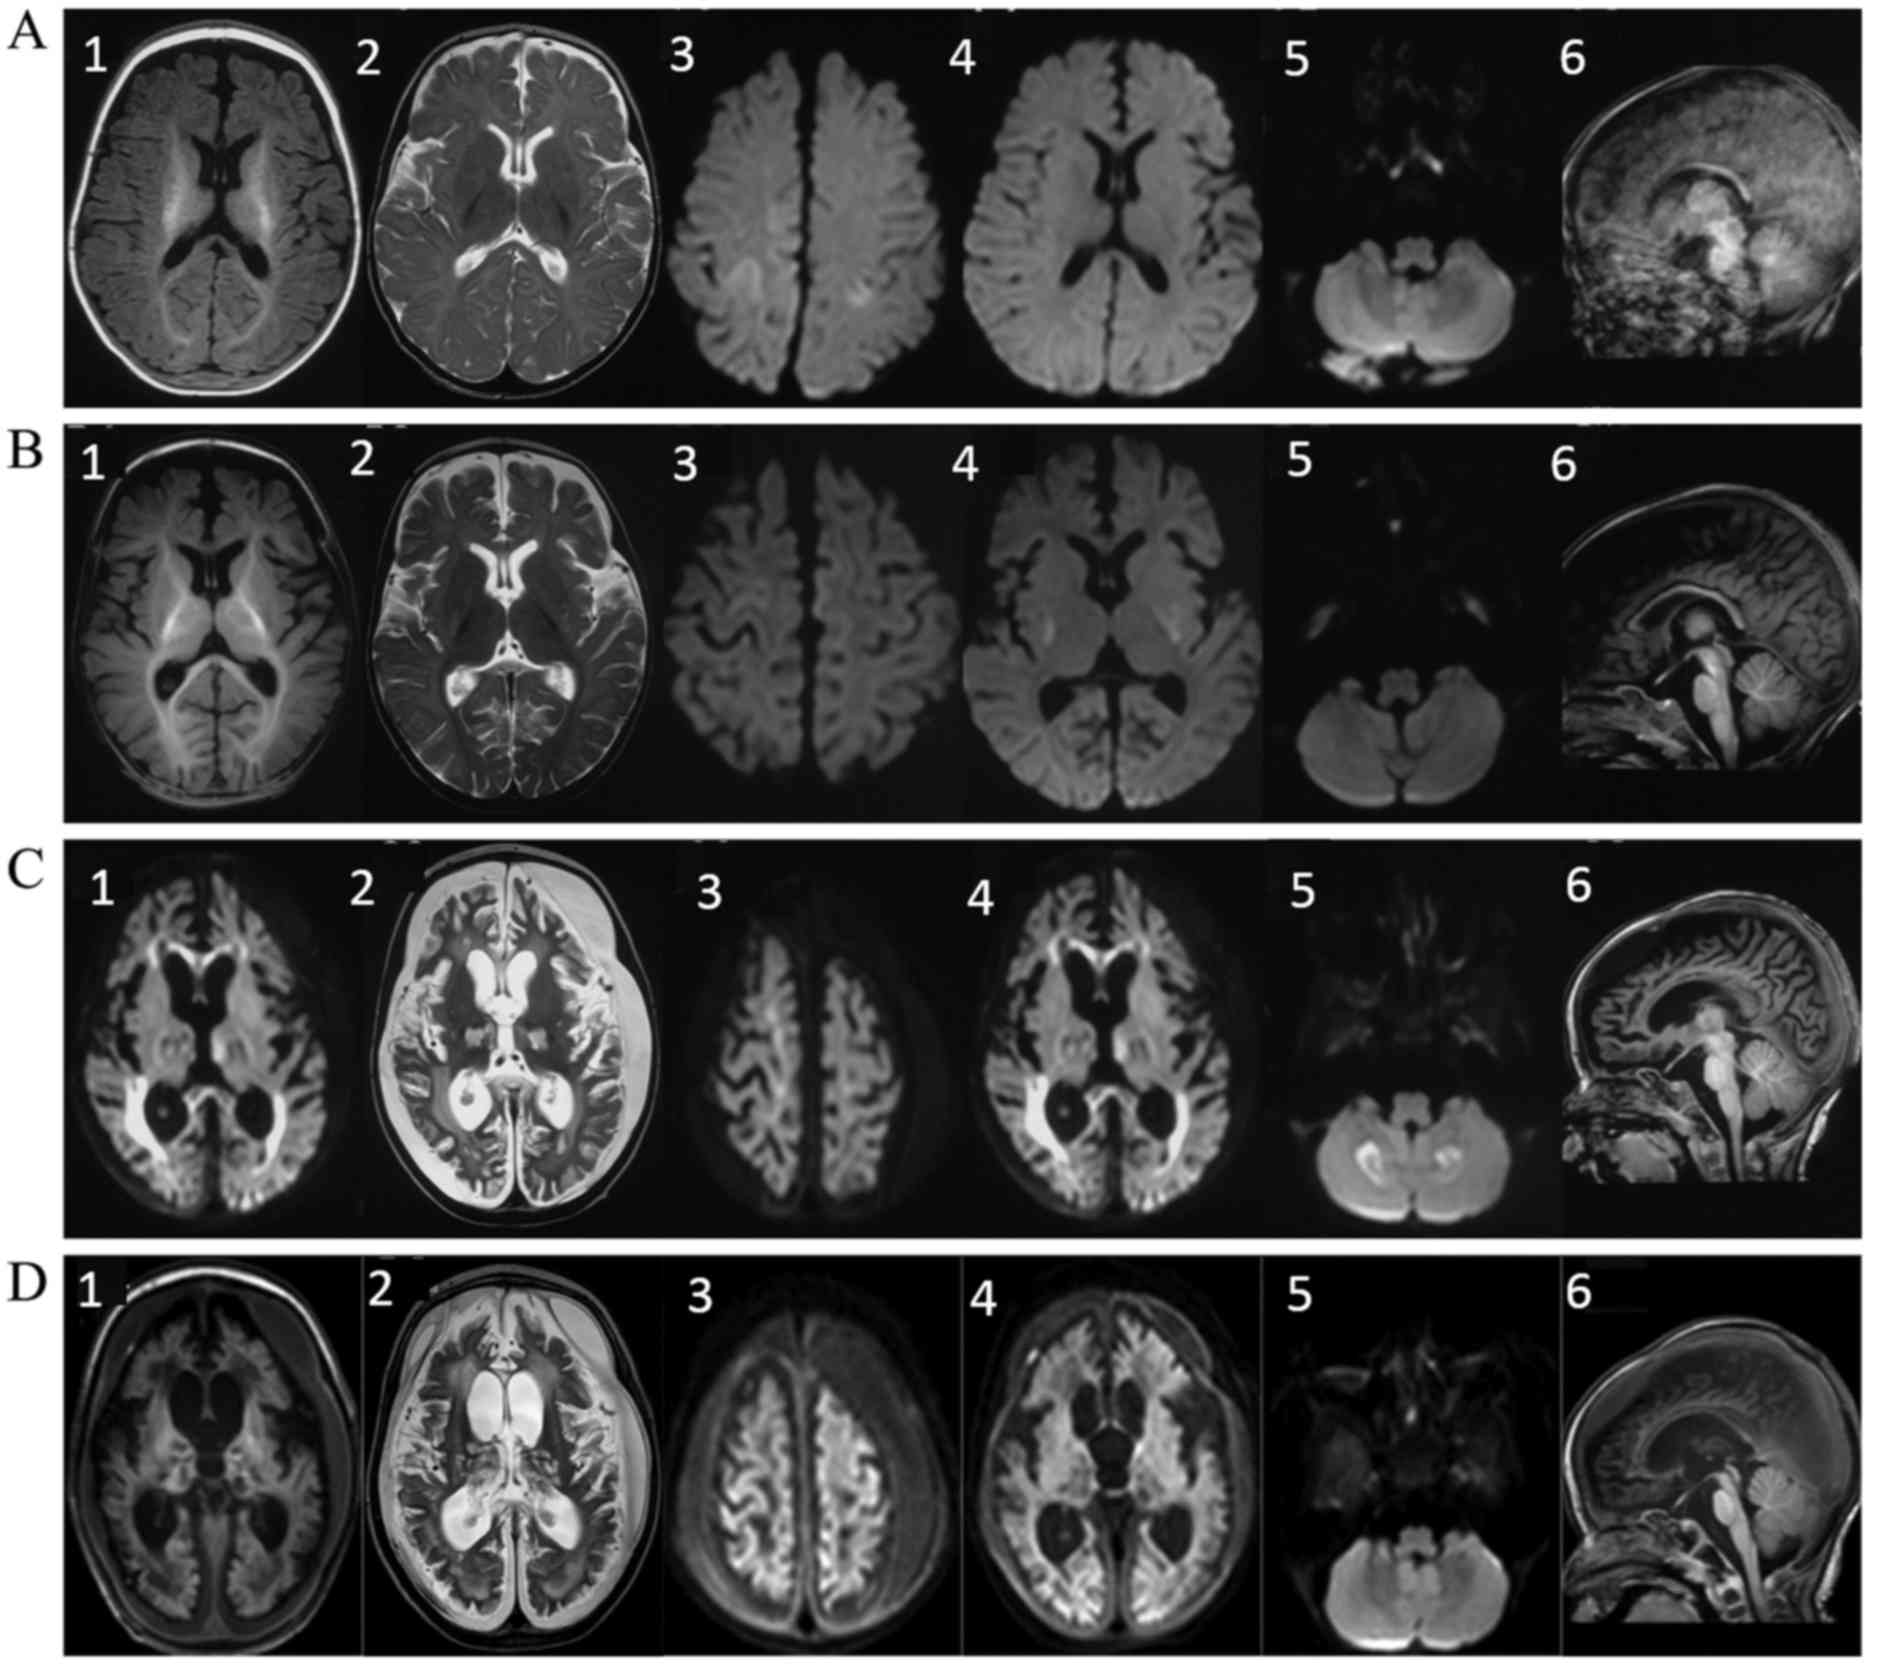

Serial brain MRI scans were performed at 4, 5, 7 and 13 months after birth, respectively (Fig. 1). Various distinctive features were observed in these scans, whereas pontocerebellar dysplasia or atrophy was absent. A high diffusion-weighted imaging (DWI) signal was detected in the frontal and parietal cerebral cortex at 4 and 5 months, which resolved after 7 months. The cortex edema was possibly associated with the frequent multifocal seizures at that time. From 5 months of age, a high signal was present on T2-weighted image (T2WI) and DWI scans in the basal ganglia and thalamus, followed by progressive atrophy. At 7 months, a symmetric high signal was detected on DWI in bilateral cerebellar hemispheres, which was suggestive of intracellular edema. In addition, in the 7-month scan, atrophy of the cerebral cortex became prominent with concomitant subdural effusions, while high DWI signals were observed in the genu and splenium of the corpus callosum, concomitant with progressive white matter depletion.

Figure 1.

Serial brain MRI scans performed in the present case. MRI scanning was performed at (A) 4 months, (B) 5 months, (C) 7 months and (D) 13 months after birth. The images show the axial T1WI (labeled as 1), axial T2WI (labeled as 2), axial DWI in the frontal and parietal cerebral cortex (labeled as 3), axial DWI in the basal ganglia and thalamus (labeled as 4), axial DWI in the cerebellar hemispheres (labeled as 5) and sagittal T1WI scans (labeled as 6). The following distinctive features were observed in the MRI scans: i) Absence of pontocerebellar dysplasia or atrophy was absent (A6, B6, C6 and D6); ii) symmetric high signal was observed on the DWI scan in the bilateral cerebellar hemispheres at 7 months of age (C5), which was suggestive of intracellular edema; iii) a high DWI signal was observed in the frontal and parietal cerebral cortex at 4 months (A3), which resolved after 7 months of age (C3); iv) atrophy of the cerebral cortex became prominent at 7 months of age, with concomitant subdural effusions (C1, C2, D1 and D2) and v) high T2WI and DWI signals were observed in the basal ganglia and thalamus at 5 months (B4), followed by progressive atrophy (C4 and D4). vi) A high DWI signal was detected in the genu and splenium of the corpus callosum at 7 months (C4), concomitant with progressive white matter depletion (C1-3 and D1-3). MRI, magnetic resonance imaging; WI, weighted image; DWI, diffusion-weighted imaging.